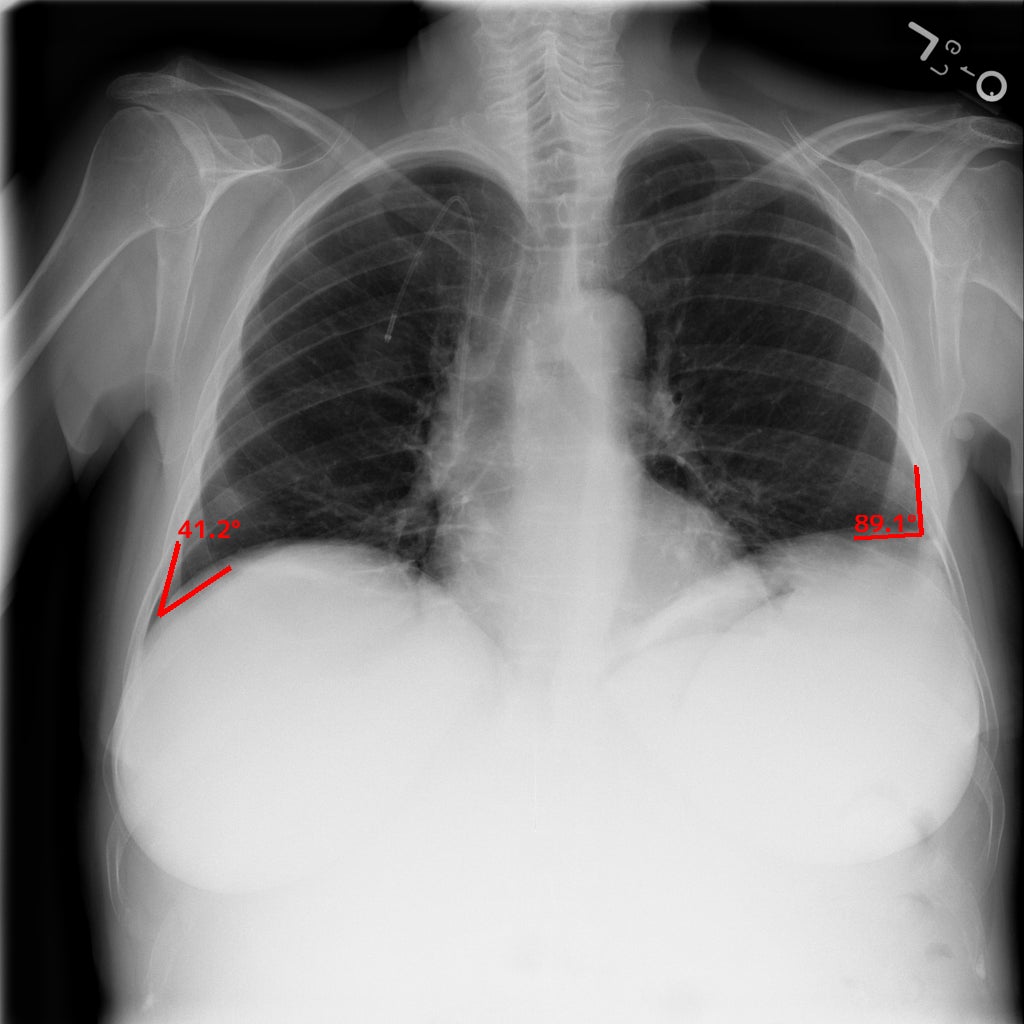

① 肋骨横隔膜角の計測

肺野境界の点のうち横隔膜と肋骨が交差する点とその点から一定の距離にある肺野境界線上の2点とのなす角[°]の計測を行い、計測結果が基準値を超えた場合に表示します。

(左はEIRL Chest Screeningによる肋骨横隔膜角の計測結果の表示例)

<助骨横隔膜の鈍化について>

通常、肺と横隔膜が形成する角は鋭角ですが、鈍化してくる場合があります。これは、胸部に通常存在しない水がたまった状態である「胸水」の所見として、心不全、腎不全、胸膜炎などが疑われます(4)。